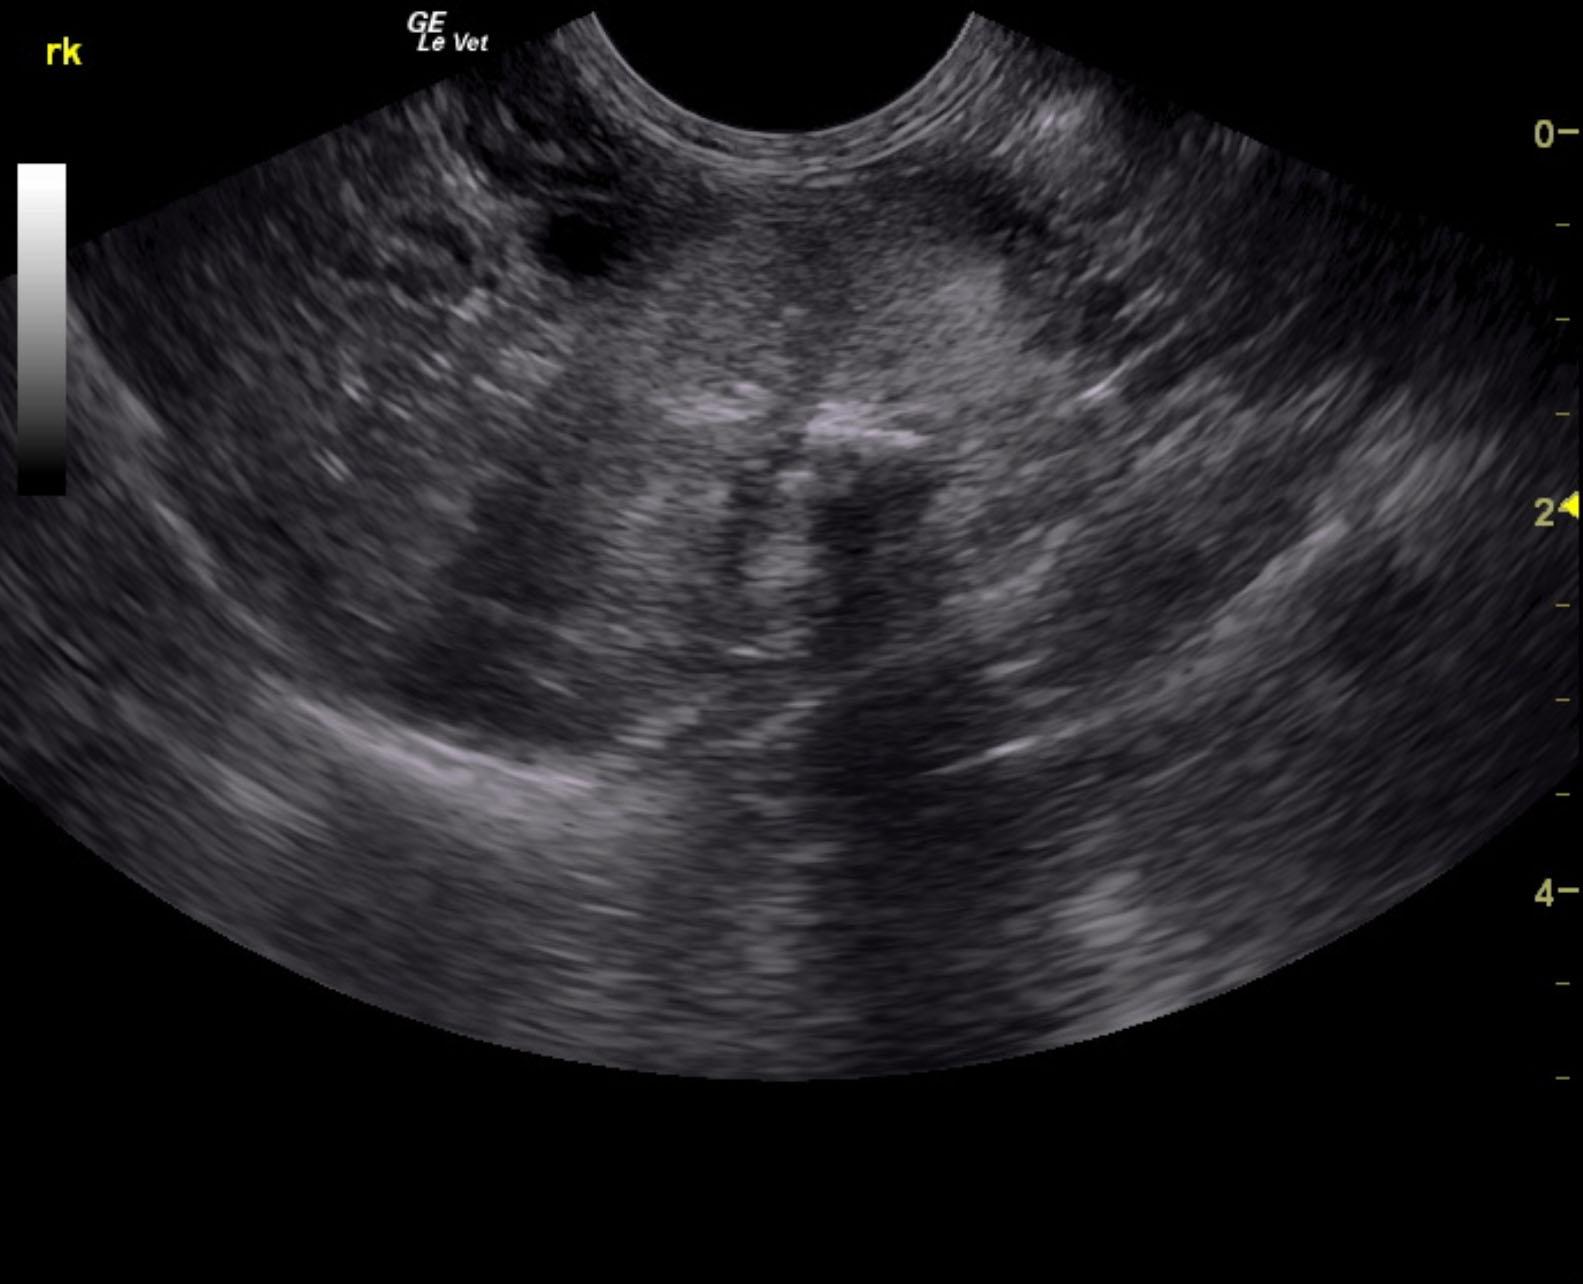

A 10-year-old neutered male Maine Coon cat with a history of lethargy and vomiting was presented for evaluation of renal failure. Cardiac murmur was present on physical examination. On urinalysis, inappropriate SG (1.014) and hematuria were evident. Blood work showed anemia, azotemia, hyperphosphatemia, and elevated liver enzyme activity. After 24 hours of fluid therapy, there was some improvement in renal values and general patient attitude.